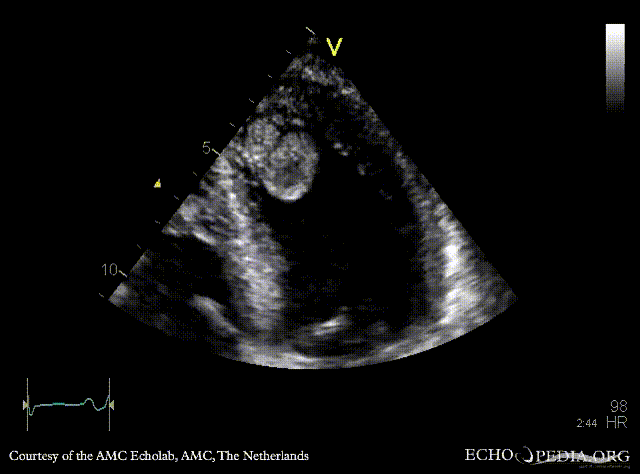

Case 142